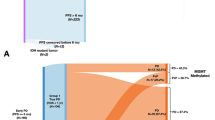

First, all TMAs were scanned for digital use. Second, a grid was developed for each TMA with the program QuPath (version 0.1.2), an open software platform for whole slide image analysis created at the Centre for Cancer Research & Cell Biology at Queen’s University Belfast, currently under development at Edinburgh University [24]. Labels of each core were added to the grid to create a look-up for each core and allowing the individual cores of the CXCR4 and HE staining to be compared one on one (Fig. 1). Subsequent scoring of the CXCR4-stained cores was performed by one researcher (SJ) who had been trained by an experienced neuropathologist (PW). In addition, 15 randomly chosen cores were scored by the same neuropathologist for interobserver agreement calculations. All cores were screened for positive (i.e. any) CXCR4 staining. Cores with established positive CXCR4 staining were then scored for intensity and extensiveness of staining of the tumor cells, using an arbitrary 4-point scale. Intensity was divided into no staining (-), subtle staining (+), moderate staining (++), and strong staining (+++). Extensiveness was defined as an estimated percentage of the area of the core showing CXCR4 staining and divided into 0% (negative), less than 25% (limited), 25–75% (partial), and 75% or higher (diffuse). In addition, the presence of different CXCR4-positive tissue components was documented, differentiating between blood vessels, cytoplasm, and/or nuclei of the tumor cells.

Example of a single tissue microarray (TMA) with CXCR4 stained glioblastoma tissue cores: (a) TMA grid in blue; green square indicating empty core due to missing tissue; orange rectangle indicating row of empty cores being part of the grid for orientation; yellow and red square representing CXCR4 positive versus CXCR4 negative glioblastoma tissue cores, higher magnification in, respectively, (b) and (c)

Next, to increase clinical relevance, CXCR4 staining scores were combined on a core level, and cut-off values were arbitrarily defined to translate core scores to a tumor level. As an example, one of the cut-off values was defined as intensity “++” and extensiveness “25–75%”; in this case, all cores with an intensity score below “++” and/or an extensiveness score < 25% were defined as being CXCR4 “negative,” while the others were CXCR4 “positive.” These results were then translated to a tumor level, where a tumor with only “positive” cores would be “CXCR4 positive,” one with only negative cores “CXCR4 negative,” and a tumor with both positive and negative cores “CXCR4 mixed.”

CXCR4 staining

Interobserver agreement calculations showed good agreement for tumor cell staining with a Kappa of 0.81, and fair agreement for the presence of stained blood vessels with a Kappa of 0.31. Seventy-eight cores (18%) were scored CXCR4 negative (no staining at all), and 18 cores (4.2%) had both strong staining as well as > 75% staining of the tumor cells. CXCR4 staining in the remaining 331 cores (78%) was highly variable (Fig. 3), also within individual glioblastoma patients. Of all cores with any staining, 255 cores (60%) showed positive cytoplasm of the tumor cells, 250 cores (59%) showed staining of the tumor cell nuclei and 127 cores (30%) showed staining of blood vessels. Fifty cores (12%) showed staining of all three of these tissue components. All four samples of normal brain tissue taken from epileptic surgery cases were CXCR4-negative. Table 1 shows the results for the three cut-offs for dichotomization of CXCR4 staining. The intra-tumor variation found in the cores remains present for all three different cut-offs.